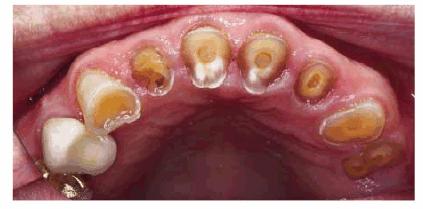

Figures 29-5A and B show a patient who did not like the

appearance of her front teeth. She felt that her maxillary central incisors

were too dark and too short. Cosmetic resin bonding was chosen as the treatment

of choice because of the immediacy of the result. Figures 29-5C and D show how the teeth were both lightened

and lengthened to provide a younger-looking smile line.

Figure 29-5A and B: This 78-year-old lady had shortened and darkened maxillary central incisors. (Reproduced with permission from Goldstein RE. Change your smile. 3rd edn. Carol Stream, IL: Quintessence, 1997:242.)

Figure 29-5C and D: Composite resin bonding was done to lengthen and lighten the central incisors. (Reproduced with permission from Goldstein RE. Change your smile. 3rd edn. Carol Stream, IL: Quintessence, 1997:242.)